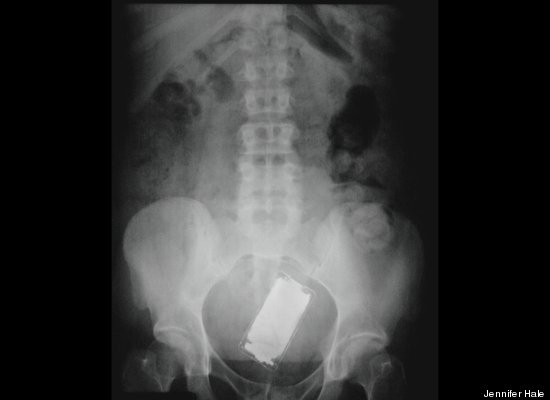

Điểm đặc biệt của cuốn sách là tập hợp 100 câu chuyện về những vật thể lạ bị kẹt một cách khó tin trong cơ thể. Ví dụ như cái kéo, cuộn dây điện hay búp bê Barbie.